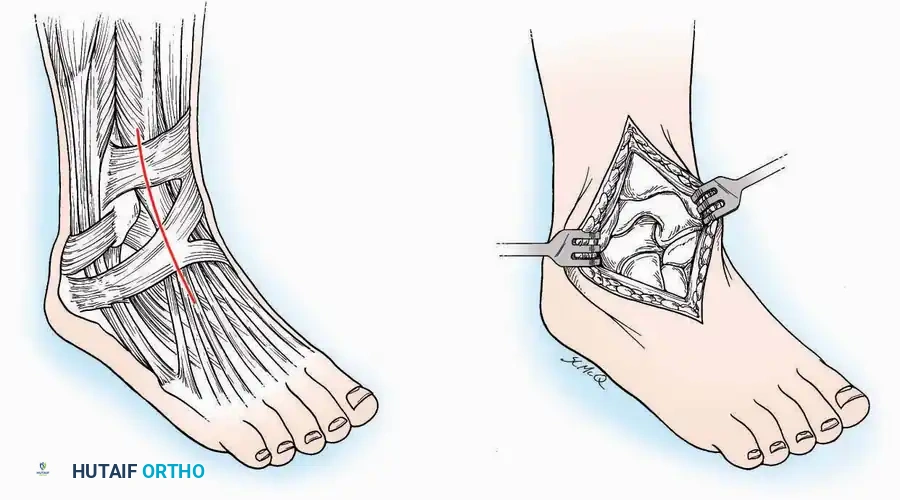

Anterolateral Approach

The anterolateral approach is widely considered the "universal incision" for the foot and ankle. It provides unparalleled access to the ankle joint, the talus, and the majority of the tarsal articulations, while safely avoiding the major anterior neurovascular bundle. The only tarsal joints inaccessible via this route are the naviculocuneiform joints (specifically the medial and intermediate).

Indications: Total talectomy, triple arthrodesis, ankle arthrodesis, and open reduction of complex talar neck fractures.

Surgical Technique:

* Incision: Begin over the anterolateral aspect of the leg, medial to the fibula and 5 cm proximal to the ankle joint line. Carry it distally over the joint, crossing the anterolateral aspect of the talar body and the calcaneocuboid joint, terminating at the base of the fourth metatarsal.

* Superficial Dissection: Incise the superficial fascia and the superior and inferior extensor retinacula down to the periosteum of the tibia and the ankle joint capsule.

* Vascular Ligation: This trajectory usually requires the identification and ligation of the anterolateral malleolar and lateral tarsal arteries.

* Nerve Protection: Retract the skin edges carefully. Identify and protect the intermediate dorsal cutaneous branches of the superficial peroneal nerve (SPN), which frequently cross the distal aspect of this incision.

* Muscle Management: Identify the origin of the extensor digitorum brevis (EDB) muscle on the lateral calcaneus. Divide it in the direction of its fibers, or detach its origin entirely and reflect it distally to expose the subtalar and calcaneocuboid joints.

* Deep Exposure: Retract the extensor digitorum longus (EDL) tendons, the dorsalis pedis artery, and the deep peroneal nerve (DPN) medially. Incise the anterior ankle capsule to expose the tibiotalar joint.

* Tarsal Exposure: Expose the talonavicular joint by dissecting deep to the extensor tendons and incising its capsule transversely. Continue laterally through the capsule of the calcaneocuboid joint. By excising the fat pad within the sinus tarsi (lateral and inferior to the talar neck), the posterior facet of the subtalar joint is brought into direct view.